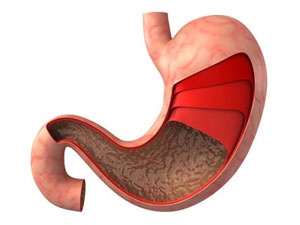

위염은 현대인의 생활습관과 밀접한 관련이 있는 질환으로, 주로 스트레스와 불규칙한 식습관이 주요 원인으로 작용합니다. 위염은 위점막에 염증이 생기는 것으로, 급성위염과 만성위염으로 나뉘며, 각기 다른 원인과 증상을 보입니다.

급성위염은 세균이나 바이러스 감염, 혹은 약물에 의해 급격히 발생하며, 만성위염은 오랜 기간 동안의 자극과 염증으로 인해 위점막이 위축되는 상태를 말합니다. 이러한 만성위염은 헬리코박터 파일로리균 감염이 주요 원인 중 하나입니다.